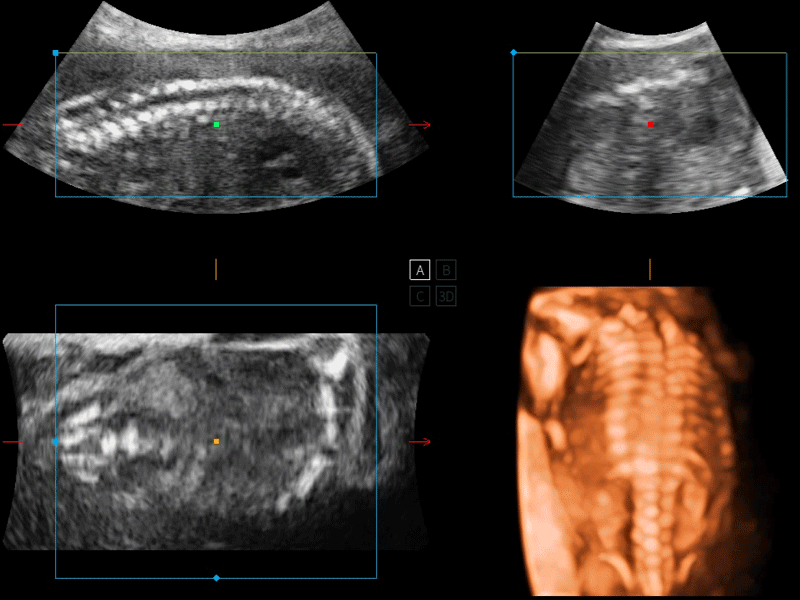

開(kāi)立醫(yī)療通過(guò)不斷的技術(shù)創(chuàng)新,為大眾的生命健康提供持續(xù)關(guān)愛(ài)。P12 Plus采用全新一代超聲成像平臺(tái),新平臺(tái)旨在將真實(shí)還原組織解剖結(jié)構(gòu)作為首要目標(biāo)。平臺(tái)采用全新集成化硬件模塊,搭載新一代芯片,系統(tǒng)性能得到大幅提升,為您的診斷提供了豐富的臨床信息。優(yōu)異的圖像表現(xiàn),豐富的探頭配置,全面的應(yīng)用功能,為您日常診斷提供了可靠的助手。

彩色多普勒超聲診斷系統(tǒng)